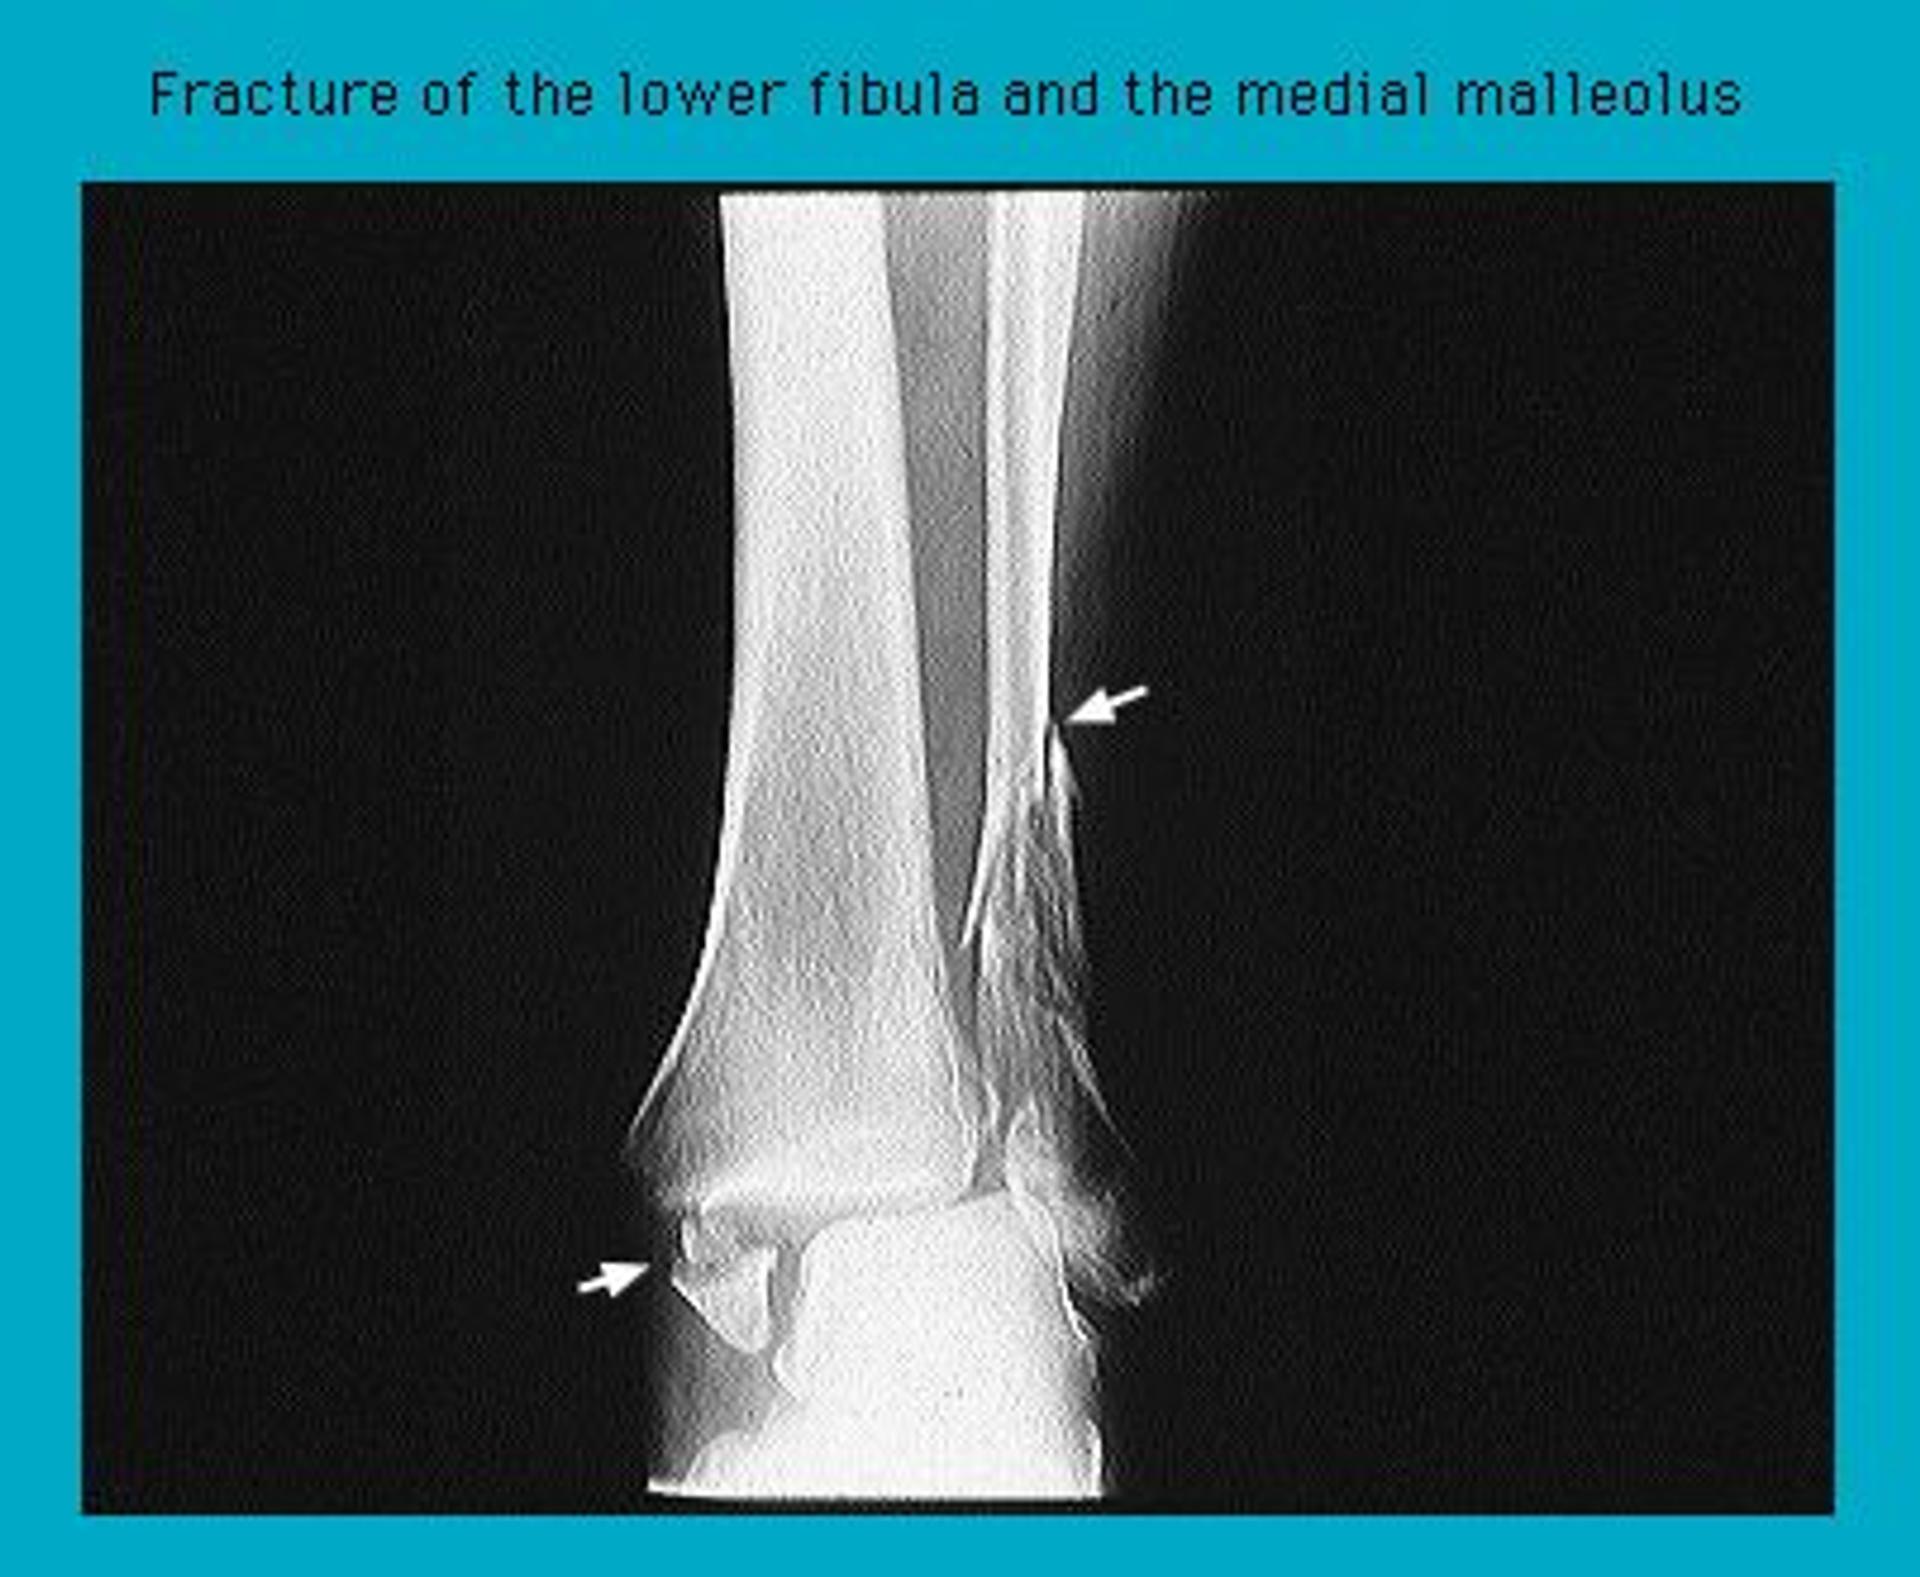

Radiograph showing Pott's fracture of the ankle